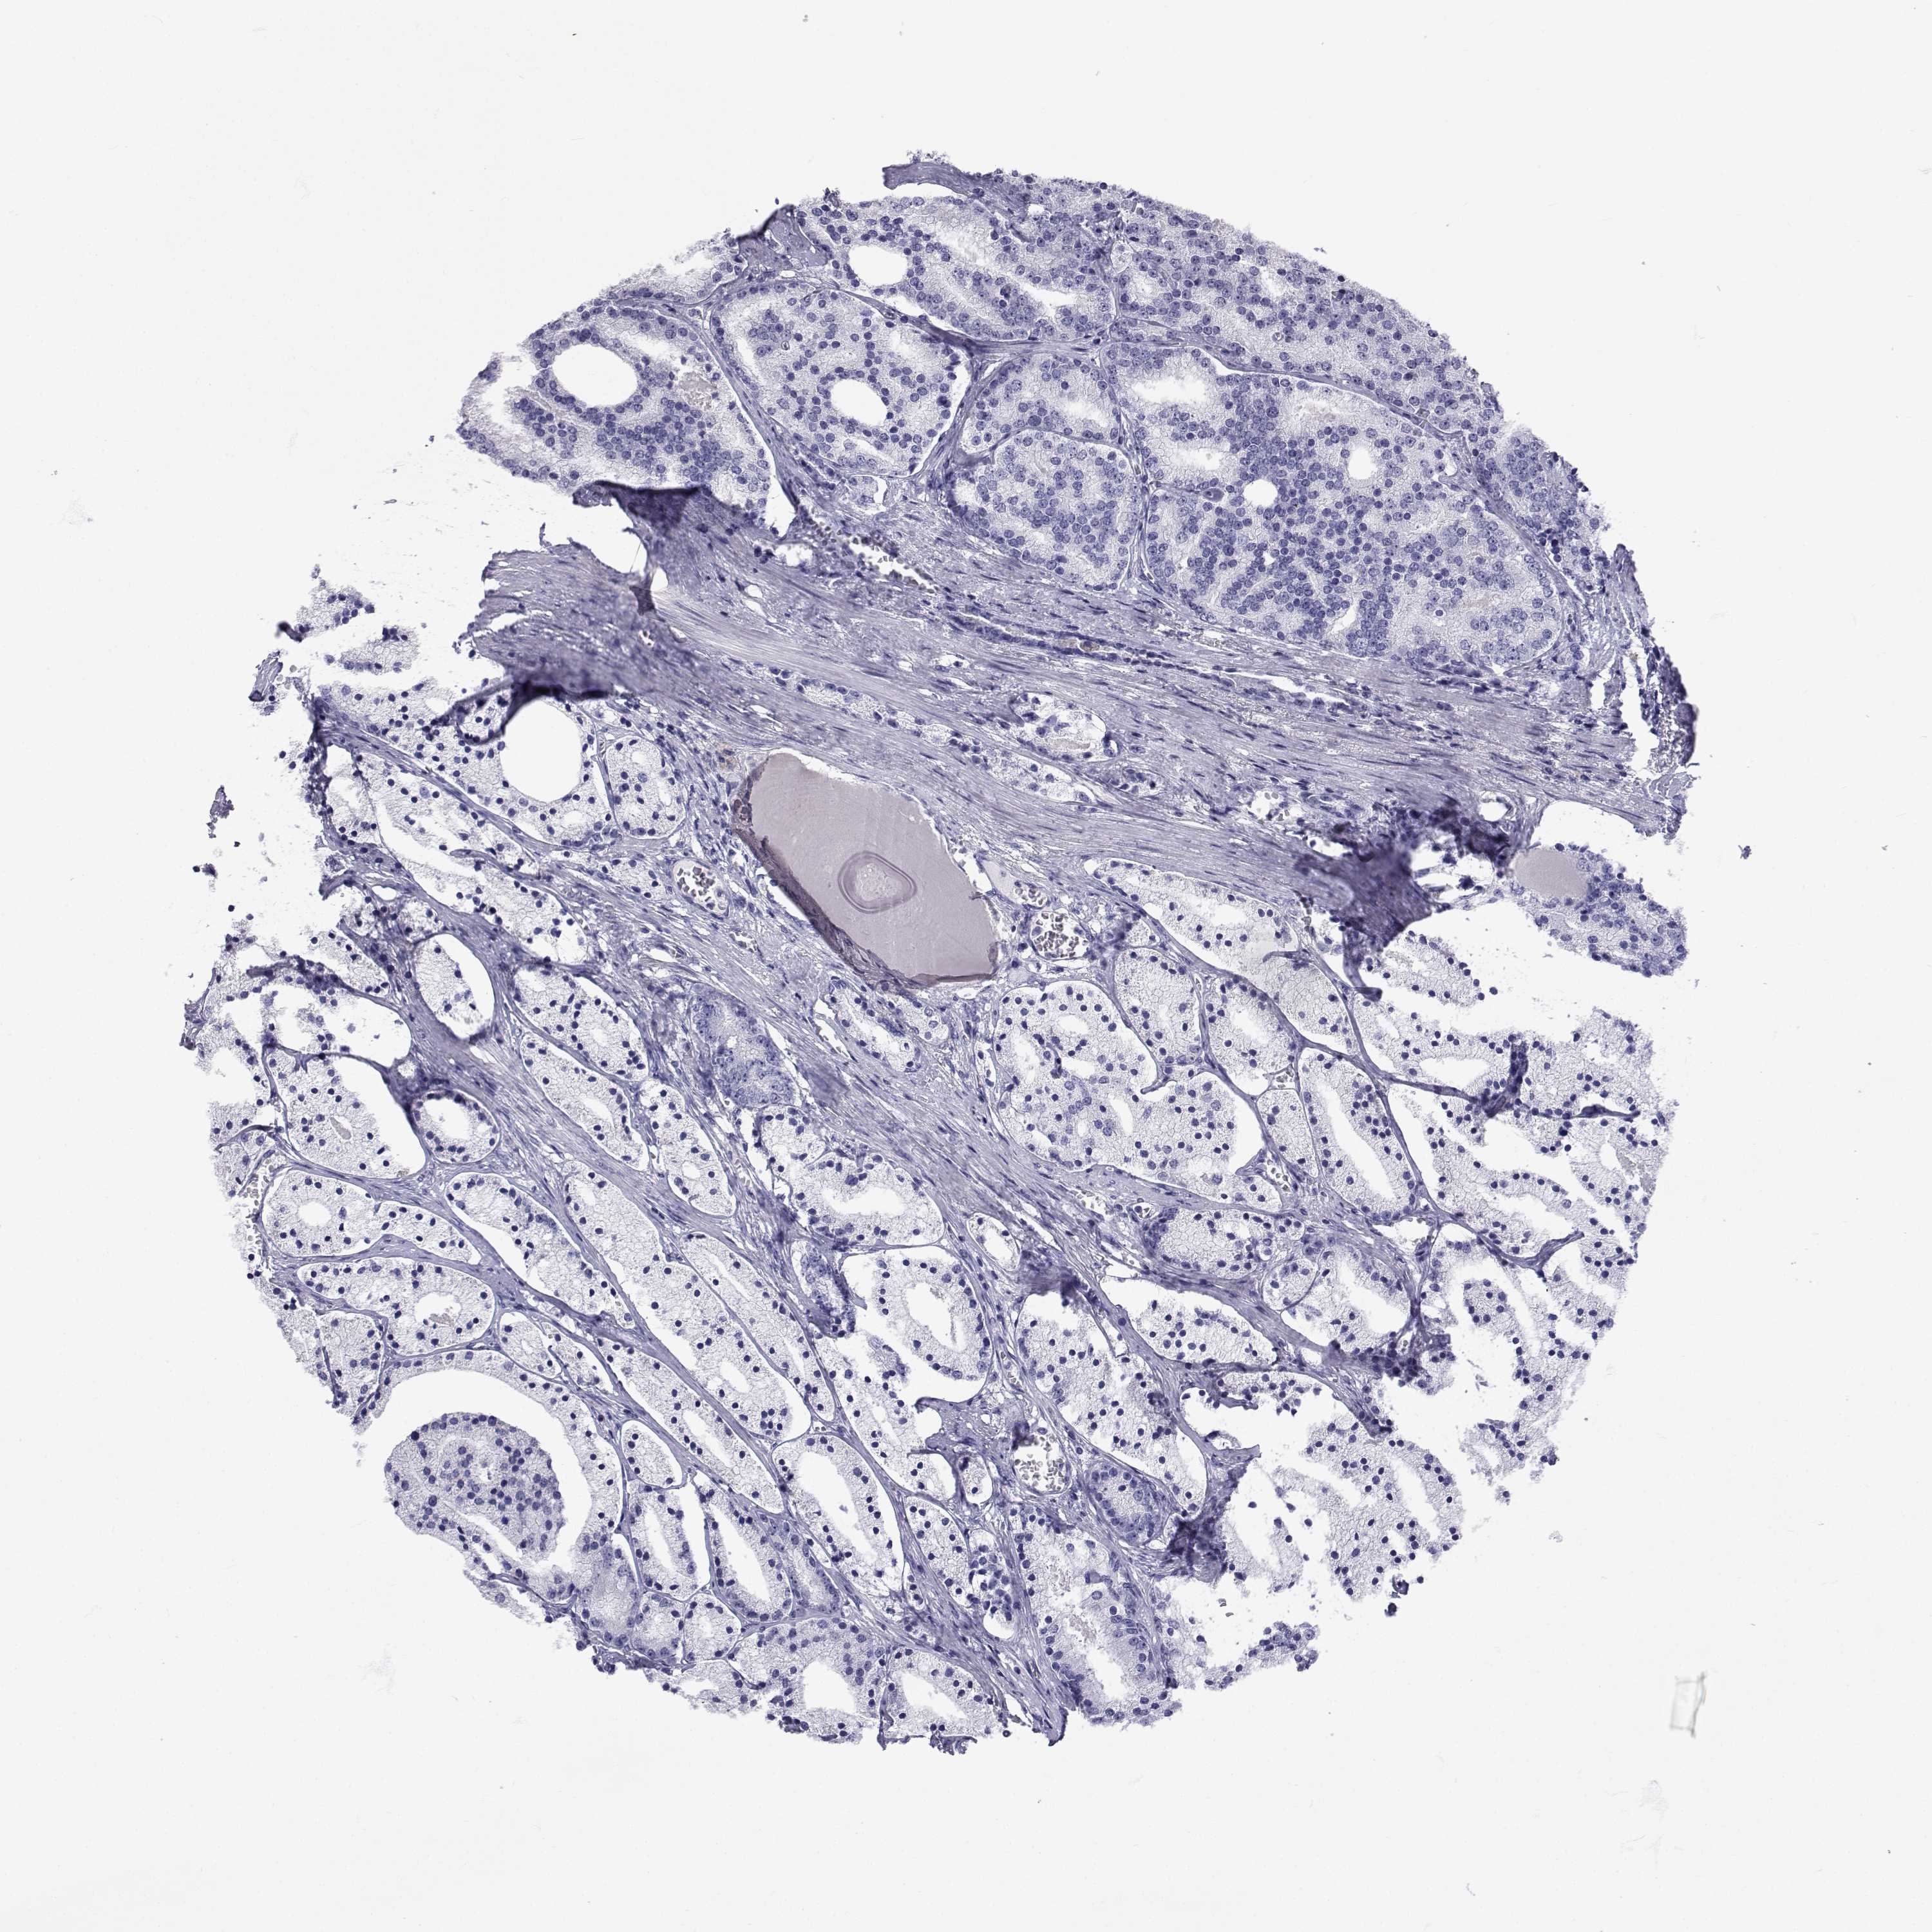

PROSTATE CANCER - Protein expressioni

A mouse-over function shows sample information and annotation data. Click on an image to view it in a full screen mode. Samples can be filtered based on level of antibody staining by selecting one or several of the following categories: high, medium, low and not detected. The assay and annotation is described here.

Antibody stainingi

Antibody staining in the annotated cell types in the current human tissue is reported as not detected, low, medium, or high, based on conventional immunohistochemistry profiling in selected tissues. This score is based on the combination of the staining intensity and fraction of stained cells.

Each image is clickable and will lead to virtual microscopy that enables deeper exploration of all samples and also displays staining intensity scores, fraction scores and subcellular localization as well as patient and tissue information for each sample.

Antibody CAB016249

Adenocarcinoma, Low grade